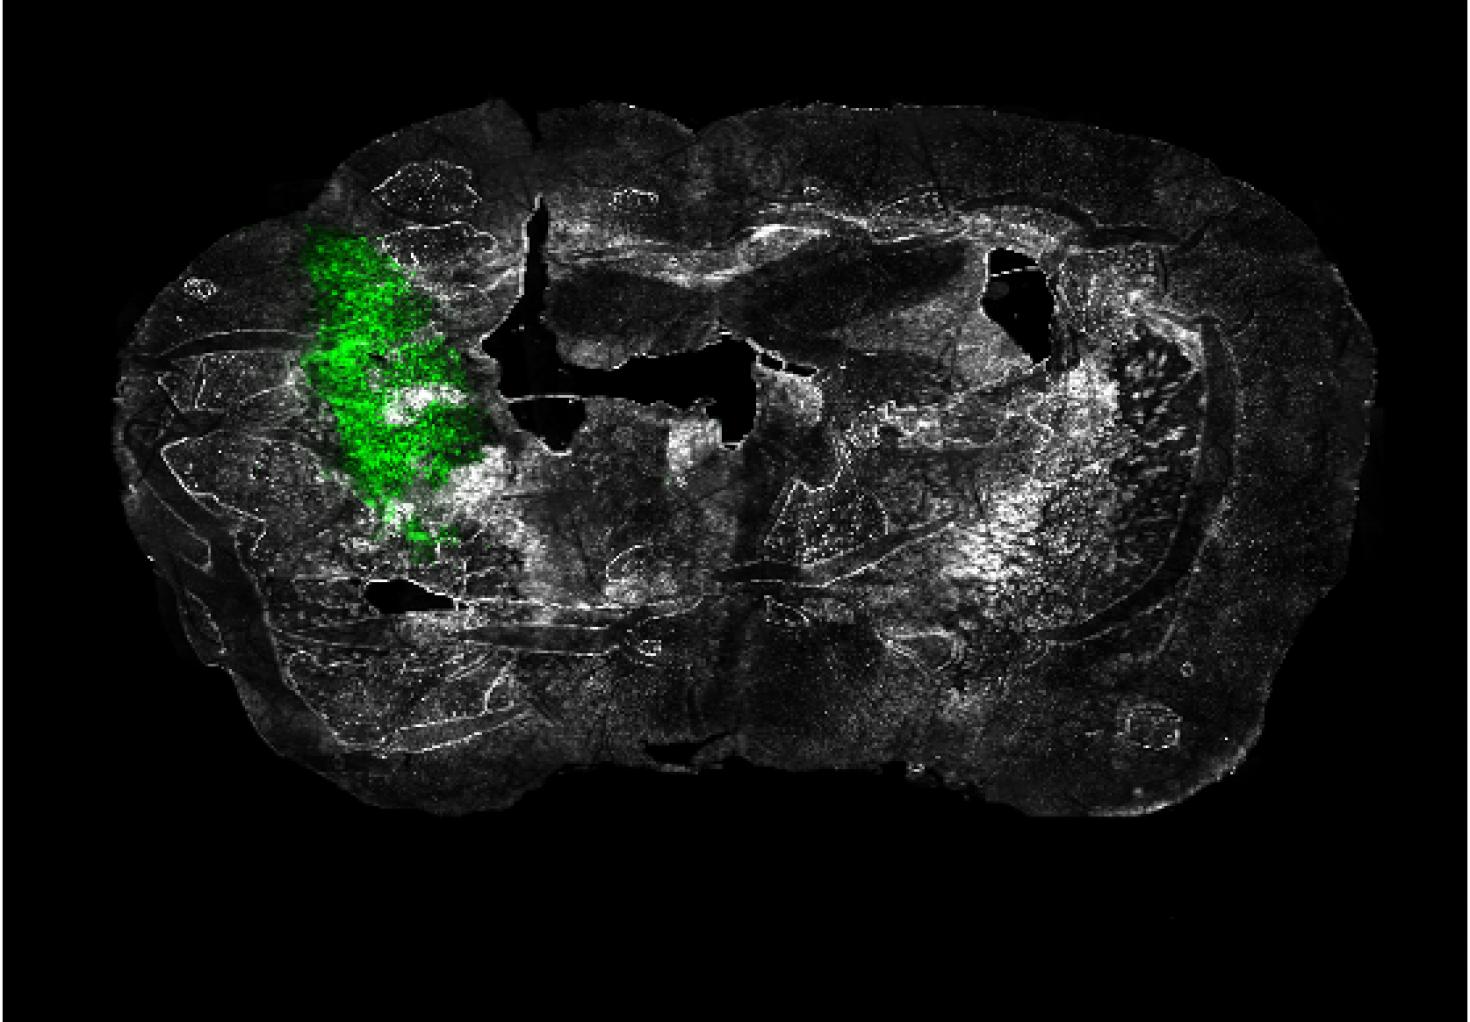

"Ex vivo coronal section of glioma cells, labeled with GFP (green), in a mouse model of glioblastoma (GBM) on day 14 of tumor development."

Image taken on Axioscan.

Author: Urbi Saha - Andrew Smith's Lab